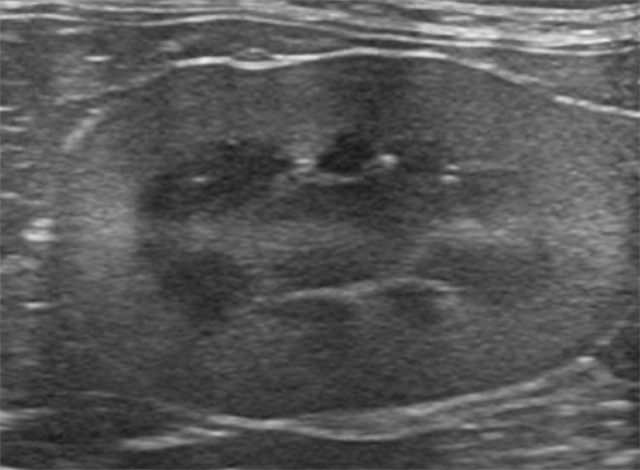

血液検査で腎臓の数値が高い時「腎臓病です」で終わらずに、腎臓に何が起こっているのか、腎臓以外の問題はないのか、をしっかり調べます。高性能の超音波検査で腎臓やその周囲に起こっている細かな異常をしっかり確認します。